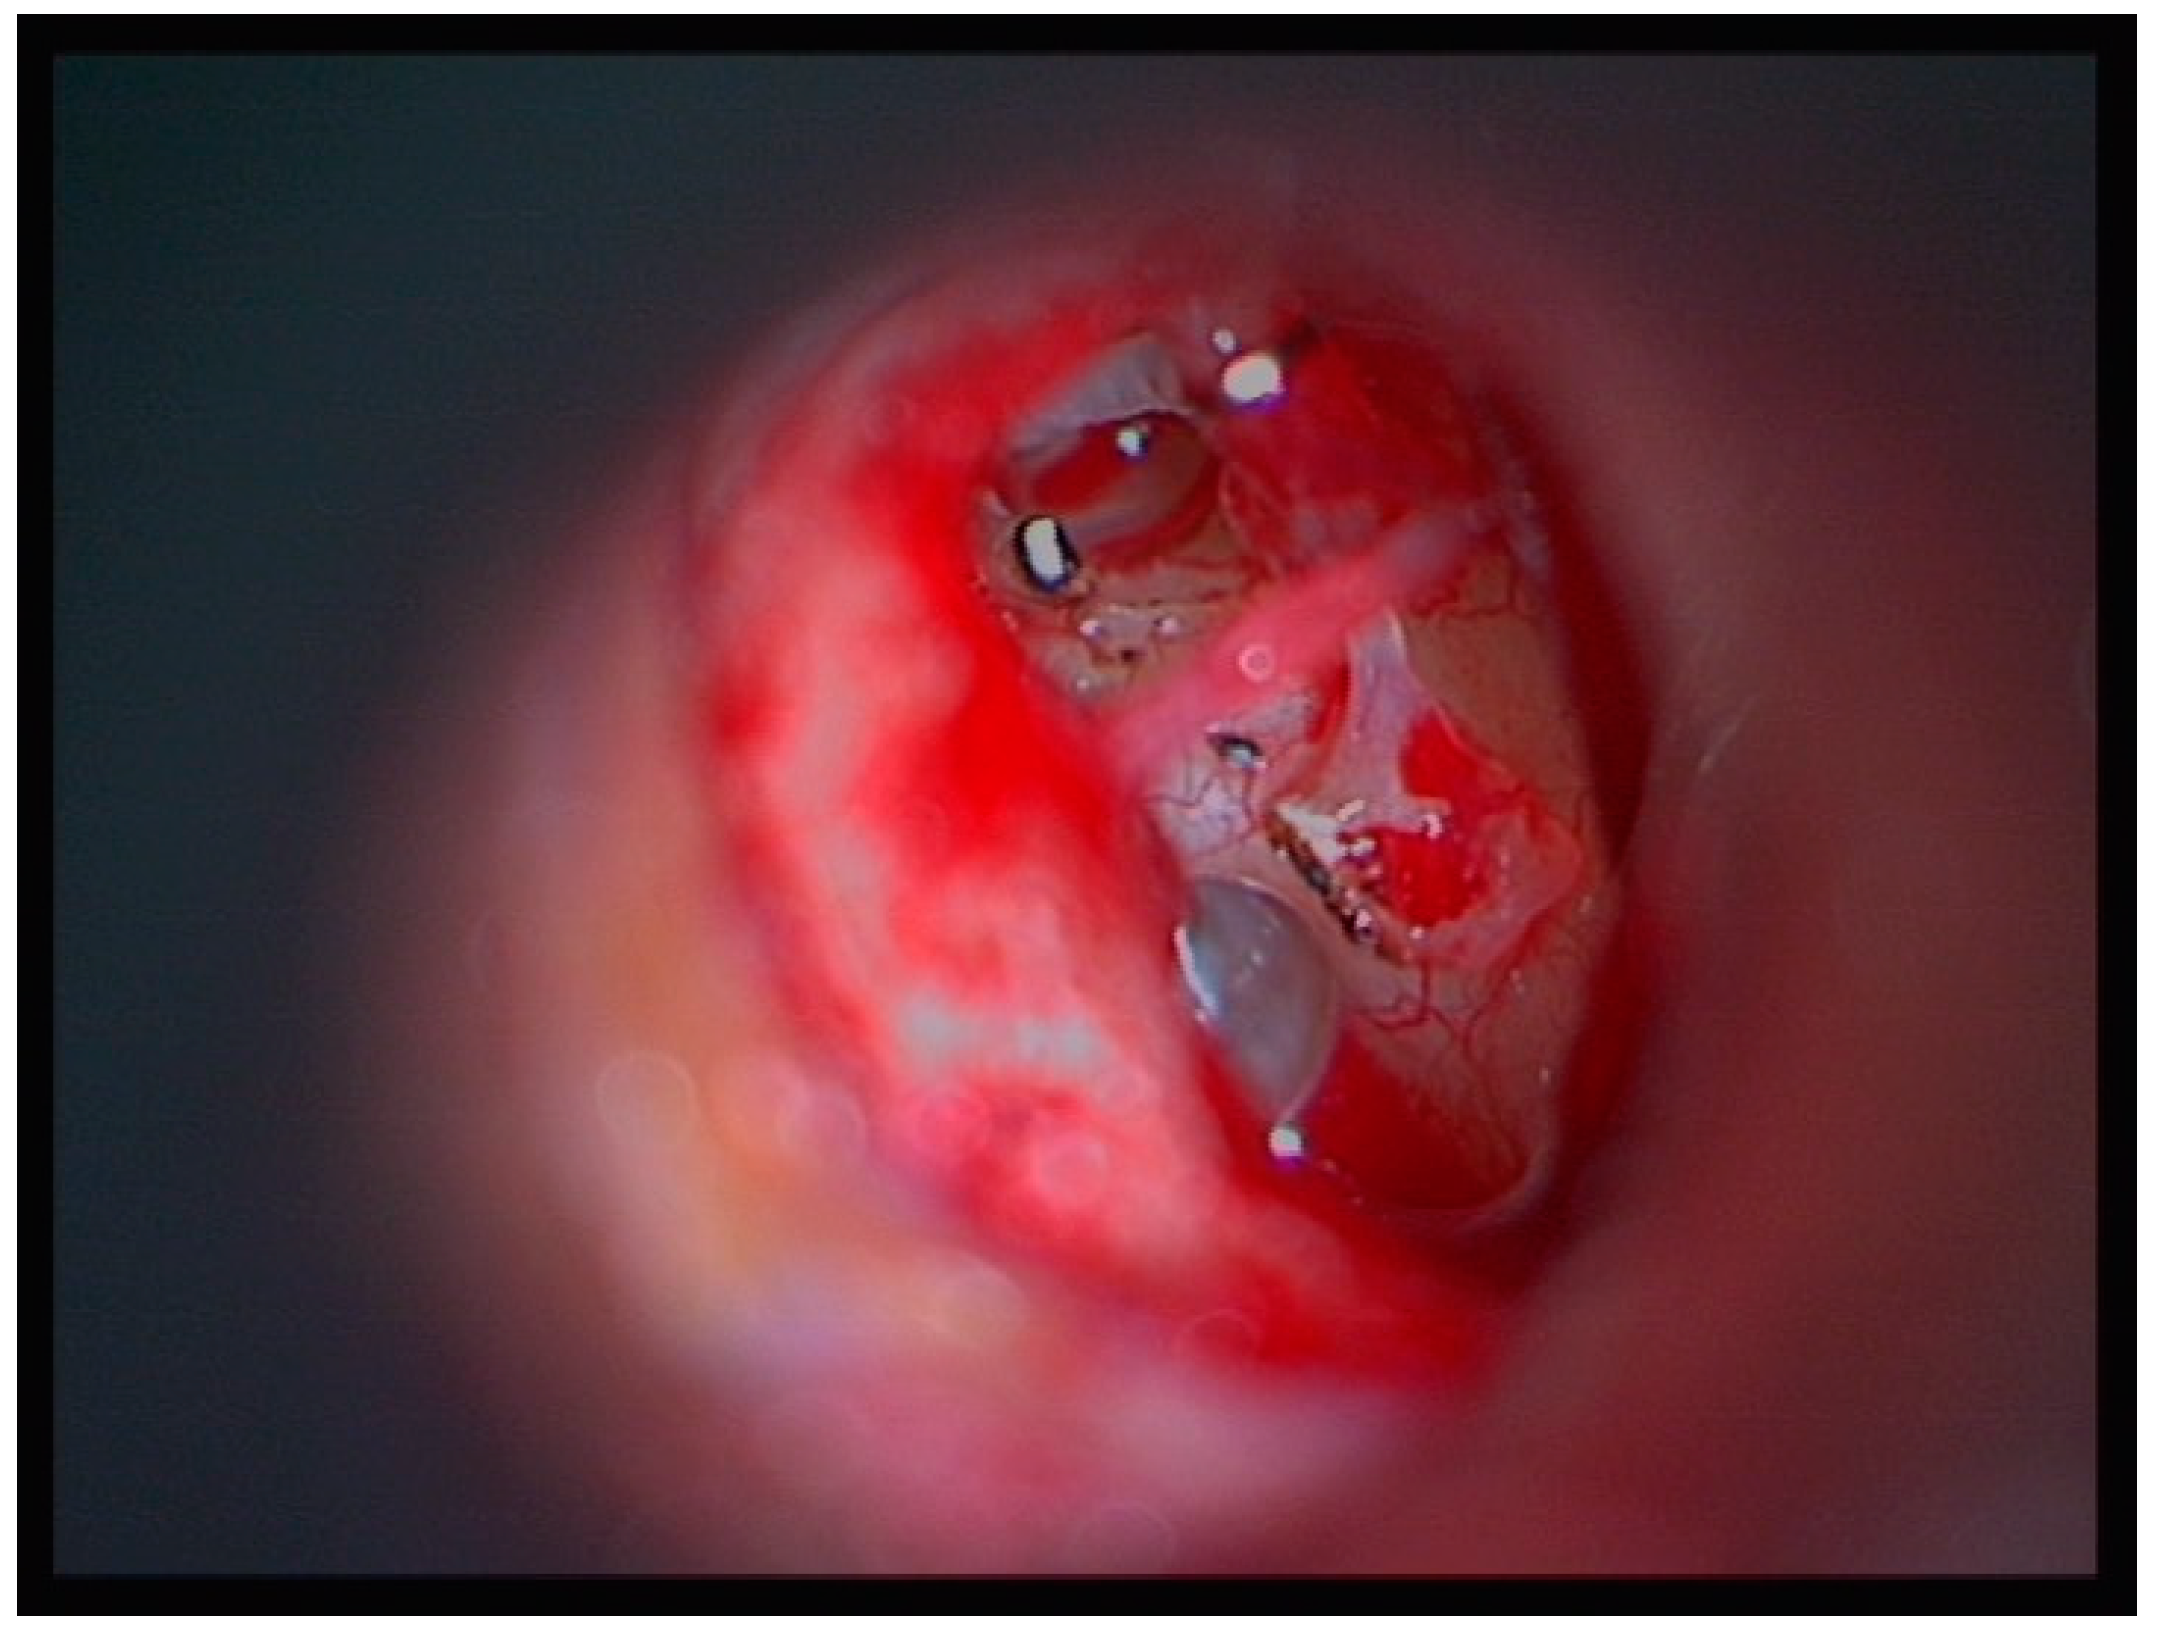

2.4. Surgical Technique